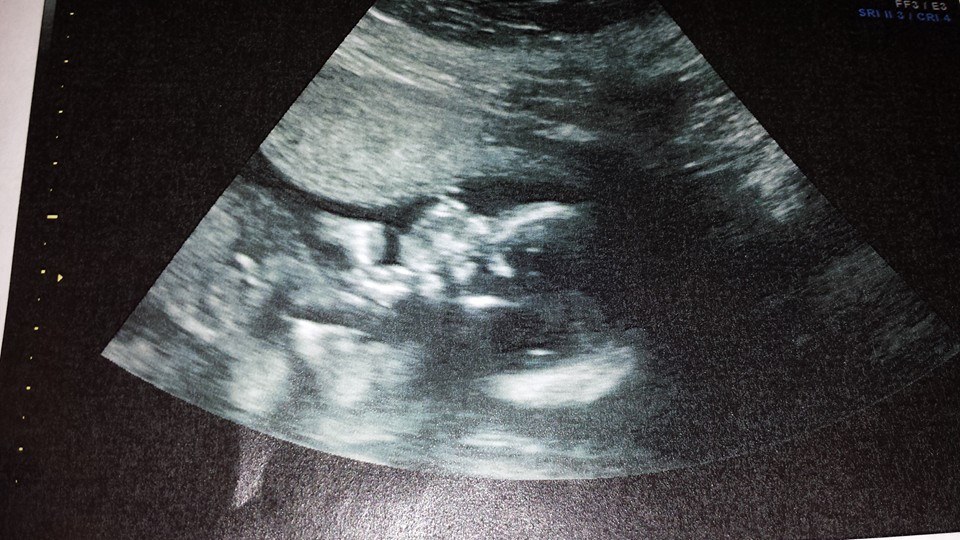

I had an appointment today for my first cervical measurement. Cervix measures about 4cm (anything over 3 is great!) TAC is holding super strong. Baby looks great too! A/s is scheduled for the 26th of this month. They also told us our c/s date!! 4/1/14!! (Im due 4/30 but going into labor is life threatening for me and baby). Yay!  Heres baby with its chin resting on its fist